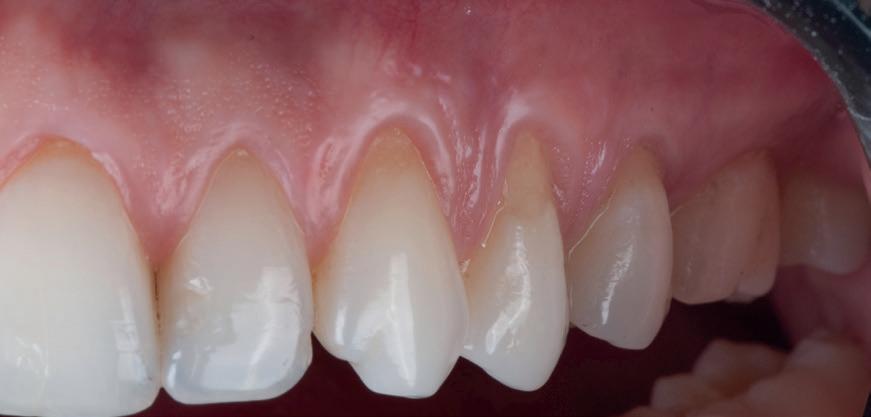

1. Situația clinică inițială.

3. Cavitate de clasa a II-a preparată.

izolarea cu digă de cauciuc, restaurarea din amalgam a fost îndepărtată complet și s-a obținut accesul la cavitatea carioasă (fig. 3-5). În ciuda proximității față de țesutul pulpar, nu a avut loc nicio expunere, iar cavitatea de clasa a II-a a fost restaurată complet cu Biodentine™ (fig. 6-8).